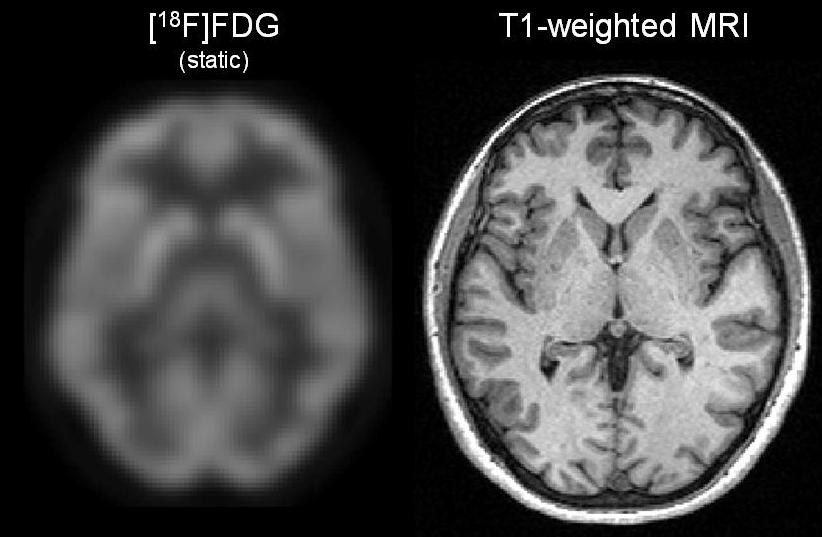

ChRDPET data analysis pipeline and reproducibility a, Main steps of

ChRDPET data analysis pipeline and reproducibility a, Main steps of Pet Test In Pharmaceutical Analysis Pet is a key experimental tool used in neuroscience drug discovery and development for assessment of exposure of new chemical entities (nces) in the central. Human in vivo molecular imaging with positron emission tomography (pet) enables a new kind of ‘precision pharmacology’, able to address. Positron emission tomography (pet) is an essential and highly significant tool to study therapeutic drug. Pet Test In Pharmaceutical Analysis.